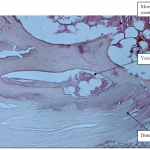

Photo INSERTIONS DE LA DURE-MERE SUR LE RACHIS Une anatomie redécouverte 31

Photo INSERTIONS DE LA DURE-MERE SUR LE RACHIS Une anatomie redécouverte 30

Photo INSERTIONS DE LA DURE-MERE SUR LE RACHIS Une anatomie redécouverte 32